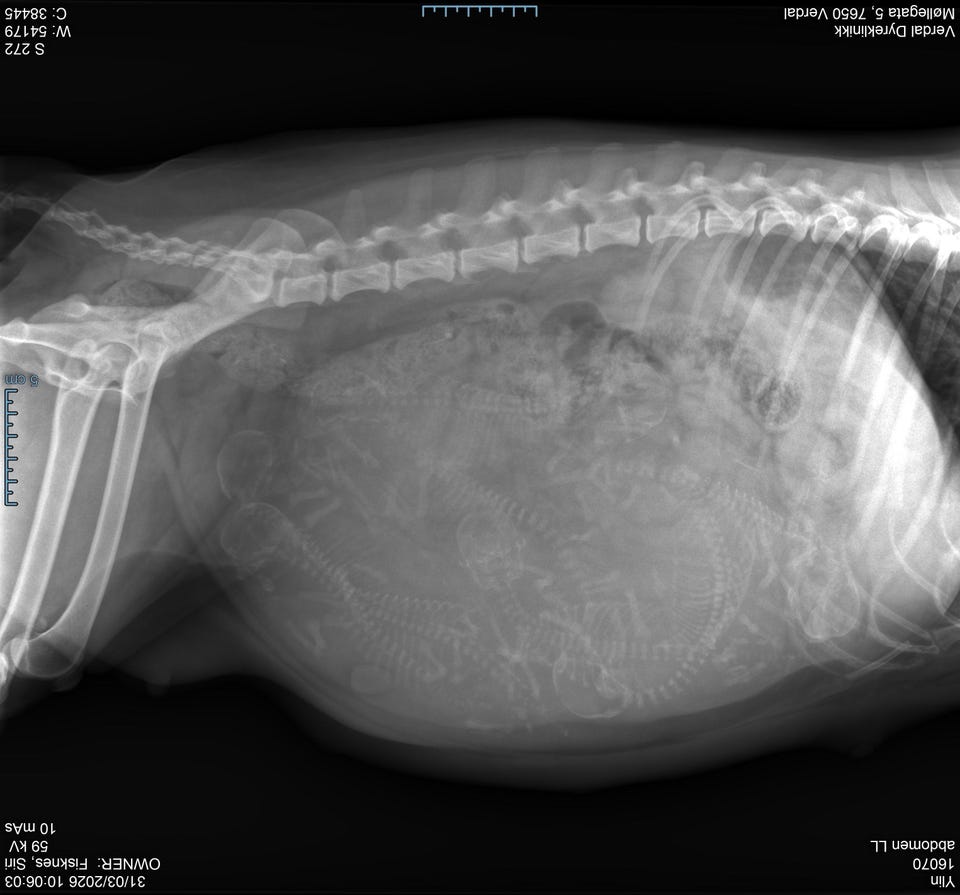

Lumikki Ylin og Jervehiets Bonzo fikk 7 valper 9. April. 5 tisper og 2 hanner.

Litt om mor Ylin:

Helse:

HD: B

Øyelyst: intet påvist

Prcd: fri

Pompes: fri